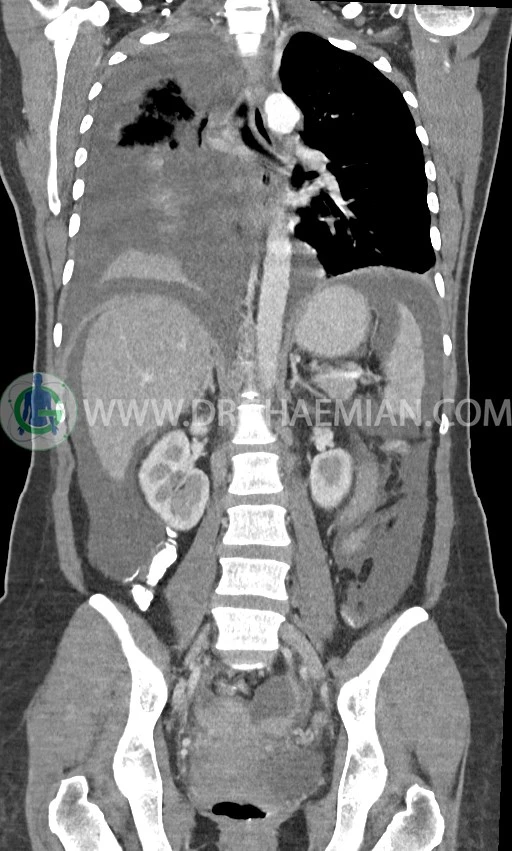

در سی تی اسکن اسپیرال ریه، مدیاستن و شکم و لگن با کنتراست خوراکی و وریدی (مولتی دیدکتور 16 با مقاطع ظریف و بازسازی های ساژیتال و کرونال) :

ضایعه ای در کبد، کیسه صفرا، مجاری صفراوی، طحال، کلیه ها، پانکراس و آدرنالها مشهود نیست.

کلیه ها کنتراست را ترشح کرده اند و نمای سیستم پیلوکالیسیل و حالب دو طرف نرمال است .

pleural effusion قابل توجه دوطرفه همراه با passive collapse سگمان های بازال (با شدت بیشتر در سمت راست)

اسیت قابل توجه در حفره شکم و لگن

لنفادنوپاتی فراوان در اطراف آئورت و IVC با حداکثر SAD= 25mm در دیواره دو طرف حفره لگن با حداکثر SAD= 20mm

مشهود است.